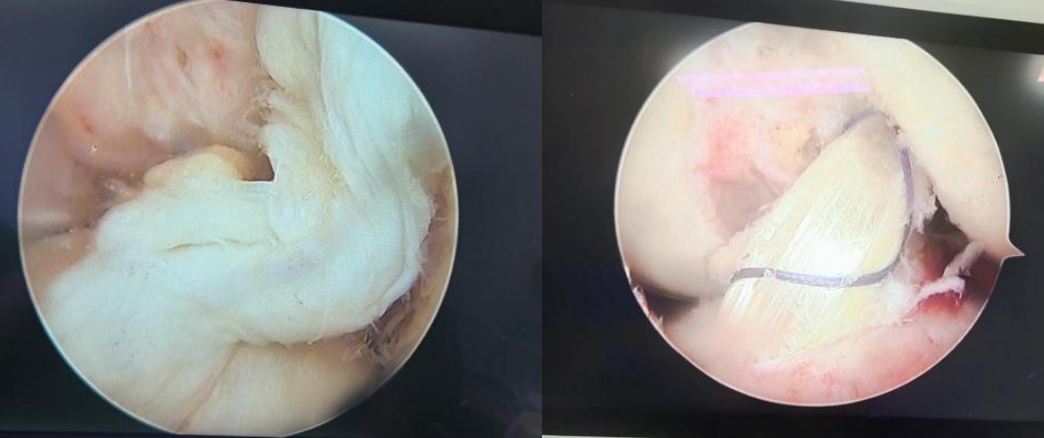

術(shù)口探查斷裂的前交叉韌帶(左)、重建后的前交叉韌帶(右)

在完善各項(xiàng)術(shù)前檢查,反復(fù)進(jìn)行病情研究及討論后,手術(shù)團(tuán)隊(duì)制定了嚴(yán)謹(jǐn)?shù)氖中g(shù)計(jì)劃:決定在膝關(guān)節(jié)鏡下采用自體肌腱行前交叉韌帶重建、內(nèi)側(cè)半月板修復(fù)術(shù)。手術(shù)過(guò)程順利,重建后的韌帶形態(tài)良好, 患者的前抽屜及Lachman、軸移試驗(yàn)均陰性,膝關(guān)節(jié)穩(wěn)定性恢復(fù)正常。術(shù)后,復(fù)查CT、 MRI 均顯示前交叉韌帶完成解剖重建,手術(shù)圓滿成功。